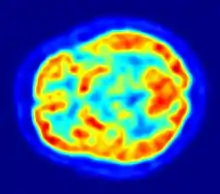

یک آزمایش استرس تالیوم شکلی از تصویبرداری جرقه ای است، که در آن مقدار تالیوم -۲۰۱ در بافت قلب در ارتباط با بافت خون است. سلولهای حیاتی زنده دارای پمپهای تبادل یون Na + / K + هستند. تالیم پمپهای K + را به هم متصل میکند و به سلول منتقل میشود. ورزش یا دیپیریدامول موجب بزرگ شدن (احیاء) عروق کرونر طبیعی میشود. این باعث میشود که سرخرگهای کرونری از ناحیه ایسکمی که در آن شریانها در حال حاضر حداکثر گسترش یافتهاند. ناحیههای آنفارکتوس یا بافت سکته قلبی" سرد" باقی میماند. تالیم پیش و پس از استرس ممکن است حوزههایی را نشان دهد که از واکنشهای قلب و عروق استفاده میکنند. توزیع مجدد نشان دهنده وجود پنهان کرونری و وجود بیماری سکته قلبی و عروقی است.[7]

جرقهنگاری تالیوم-۲۰۱ (به انگلیسی: Thallium-201 Scintigraphy) نوعی جرقهنگاری در پزشکی هستهای است.[11]

در این روش از رادیوایزوتوپ تالیوم-۲۰۱ استفاده میشود. ماده را نخست در یک ورید تزریق کرده و تصاویری را از تریسر در حال عبور از قلب را ثبت میکنند. نقاط به اصطلاح سرد تصویر، متناظر با نواحی است که در آنها سکته قلبی رخ دادهاست. همانند اسکن سستامیبی تکنیتیوم-۹۹ام، میتوان از این ماده در آزمایش قلبی موسوم به exercise tolerance test استفاده نمود که کمک میکند نواحی خونی کمجریان به ماهیچههای قلبی مشخص شود.[12]